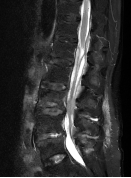

收治入院后感染科积极安排超声引导下腰背部软组织积液穿刺,抽出淡红色液体0.5ml,细菌培养提示金黄色葡萄球菌。经过2个月的针对性抗感染治疗,张奶奶的腰痛症状逐渐好转,从最开始的翻身困难、下肢抽痛,到行走自如。期间动态复查腰椎核磁,可见脓肿逐渐吸收,出院后3个月张奶奶再次来复查,脓肿已完全吸收,张奶奶的生活回到正轨!

治疗前

治疗2周